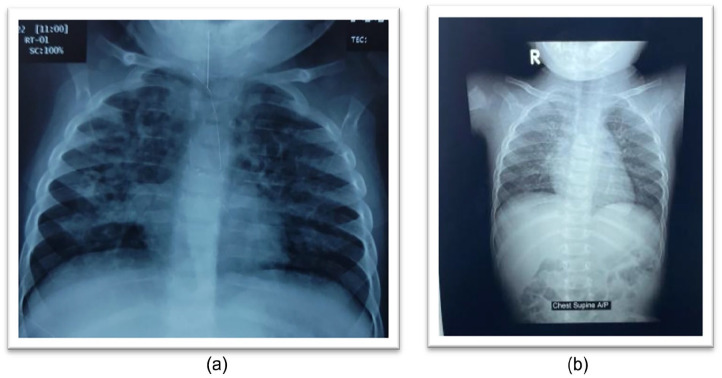

A 7-month-old girl had been suffering from progressively deteriorating pneumonia despite getting multiple courses of broad-spectrum antibiotics as well as anti-fungal drugs for adequate duration. To find out the cause behind this deterioration, the patient underwent thorough clinical and relevant laboratory evaluation including chest radiology & imaging, screening for primary immune deficiency disorders (PID), cystic fibrosis, tuberculosis, invasive fungal pneumonia, congenital heart disease, covid pneumonia, TORCH etc. but failed to solve the mystery. Upon further detailed re-evaluation, it was discovered that the child had a history of being forcefully fed lentil-based khichuri (a rice-lentil mixed dish) during her weaning process and diagnosis was finally confirmed as hypersensitive pneumonia due to lentil aspiration by a high level of IgG, specific to lentil antigen. Treatment was commenced with prednisolone resulting in significant improvement in her clinical and radiological condition within 72 hours.

Abstract Image